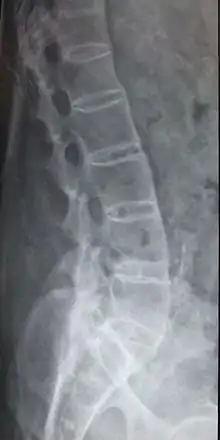

Les radiographies du bassin permettent de visualiser un contour estompé de l'articulation sacro-iliaque, voire un élargissement de la jonction. À un stade plus avancé, elles mettent en évidence des érosions ou des ossifications aux endroits où s’insèrent les enthèses. Parfois, la colonne vertébrale paraît complètement ossifiée et fusionnée avec l'aspect de « tronc de bambou » dans les formes évoluées.

Dans les formes les plus évoluées, il peut y avoir une ossification complète avec soudure de tous les os concernés : les vertèbres lombaires forment un seul bloc. Cela arrive au niveau du dos mais aussi au niveau du cou.

De temps à autre surgissent des douleurs importantes qui alternent avec des épisodes indolores. Généralement survient la formation des calcifications des ligaments d'une articulation et plus particulièrement des ligaments se trouvant en avant et sur les côtés permettant l'union des vertèbres, entraînant ce que l'on appelle la pelvispondylite rhumatismale. Celle-ci génère des déformations caractéristiques de la colonne vertébrale. Progressivement, la lordose — le creusement des reins — disparaît et les muscles constituant les fesses fondent. Au niveau du thorax en arrière, la cyphose — l'arrondi du thorax — est accentuée : accentuation de la bosse thoracique. Quand il existe une atteinte du rachis cervical, la tête semble comme projetée vers l'avant. L'atteinte de la hanche entraîne une ankylose pouvant conduire à une flexion de celle-ci, compensée par une flexion des genoux.